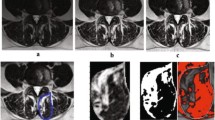

Kenneth A.Weber, Madeline Hess’s T1 axial Muscle Segmentation uses V-Net. Kenneth A.Weber’s performance is (Left DSC:0.862 ± 0.017, Right DSC: 0.871 ± 0.016) lower than Madeline Hess’s performance (DSC:0.88). This is because the elements that make up v-net are different. Table 4 compares these differences. We also compared the performance of the 3D CNN and 2D CNN. In E. O. Wesselink's study, the objective was to compare the performance between 2D convolutional neural networks (CNNs) and 3D CNNs. While 2D CNNs are designed to extract features from 2-dimensional images, 3D CNNs do so from 3-dimensional volumetric data. In this study, data augmentation techniques were applied, and the True positive rate (TPR) for right-sided muscles specifically the multifidus, erector spinae, and psoas major was compared between the two models. As indicated in Fig. 2, the 2D model demonstrated superior performance in identifying muscles when compared to the ground truth, outperforming the 3D model. The performance of the segmentation model varies depending on the presence and severity of spine pathology [19]. In Benjamin Dourthe's study, the Dice Similarity Coefficient (DSC) values for three specific Regions of Interest (ROI) were compared between healthy individuals and those with Adult Spinal Deformity (ASD). The ROIs included the vertebral body, psoas major, and multifidus erector spinae. The study uses data from five different sets to make an in-depth comparison of how well these anatomical regions are identified in both groups. Based on the analysis, the lumbar region in healthy individuals performed better in terms of ROI identification compared to those with ASD. Figure 3.